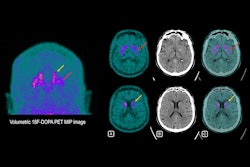

Cerebral F-18 FDG-PET of a 73-year-old man with overlapping features of corticobasal degeneration (CBD) and progressive supranuclear palsy (PSP). The top row shows axial sections at the level of the basal ganglia and mesencephalon of F-18 FDG, CT, and statistical maps. The bottom rows show statistical surface projections with standard deviations from healthy subjects. Note the asymmetry and involvement of the basal ganglia pointing towards CBD and the involvement of mesencephalon and mesial frontal cortex pointing towards PSP. Image and caption courtesy of EJNMMI Research through CC BY 4.0.The group identified 156 patients referred for a brain F-18 FDG PET scans between 2017 and 2019 for suspicion of atypical parkinsonism, with imaging analyzed by a nuclear medicine specialist with more than 10 years of experience in PET neuroimaging. The reference standard for comparison was each patient's follow-up clinical diagnosis.